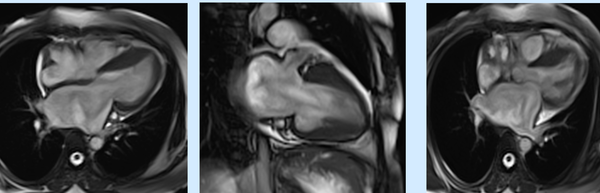

The new 2020 Padua criteria explained